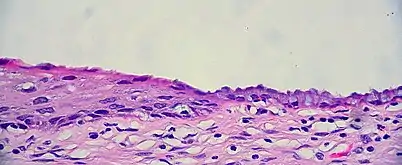

The endocervical mucosa is about 3 mm (0.12 in) thick and lined with a single layer of columnar mucous cells. It contains numerous tubular mucous glands, which empty viscous alkaline mucus into the lumen.[4] In contrast, the ectocervix is covered with nonkeratinized stratified squamous epithelium,[4] which resembles the squamous epithelium lining the vagina.[17]: 41 The junction between these two types of epithelia is called the squamocolumnar junction.[17]: 408–11 Underlying both types of epithelium is a tough layer of collagen.[18] The mucosa of the endocervix is not shed during menstruation. The cervix has more fibrous tissue, including collagen and elastin, than the rest of the uterus.[4]

The squamocolumnar junction of the cervix, with abrupt transition: The ectocervix, with its stratified squamous epithelium, is visible on the left. Simple columnar epithelium, typical of the endocervix, is visible on the right. A layer of connective tissue is visible under both types of epithelium.